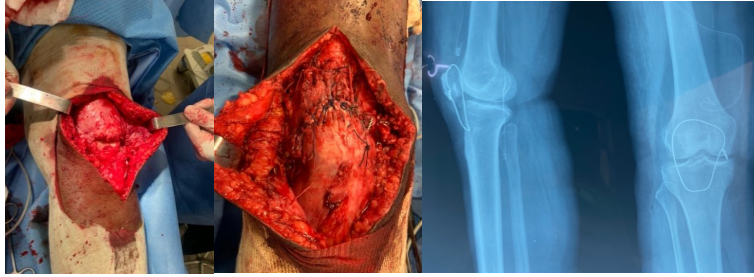

Mrs. , a 50-year-old woman with no significant medical history, presented 45 days after a closed injury of the left knee caused by a fall. Initial management had been performed in a non-specialized center. On examination, she walked with a limp. There was loss of active knee extension and a palpable defect along the patellar tendon, with intact skin. Standard radiographs revealed patella alta with a Caton-Deschamps index of 2 (Fig. 3). Magnetic resonance imaging (MRI) confirmed rupture of the patellar tendon (Fig. 3). Surgery was performed under spinal anesthesia with the patient supine. Intraoperative findings revealed a midsubstance rupture of the tendon. Tendon repair was performed and reinforced with a protective frame (Fig. 4). At 12-month follow-up, the patient had recovered active knee extension.

Figure 4: Intraoperative view of the rupture (a), tendon repair with protective frame (b), and post-operative control radiograph (c) – Patient 2.